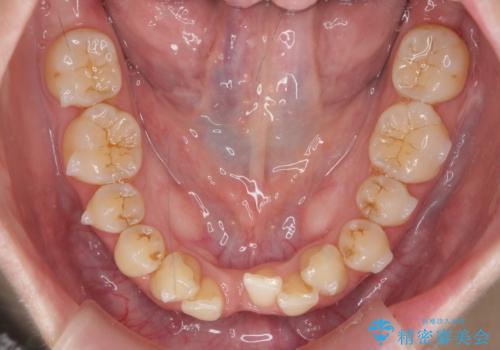

前歯のガタつき インビザラインで 下の前歯を1本抜歯

- 前歯のがたつきを主訴に来院。マウスピース矯正を希望されました。

治療にあたり、下の前歯を一本抜歯しています。

非抜歯で無理に治療をしようとすると、下の前歯の骨が薄く歯ぐきが下がったり、歯がぐらついたり、がたつきが完全にとれないリスクがあることを説明しました。

下の前歯が3本になるため、上下の正中は合わない仕上がりとなりますが、正中を合わせるには上下左右4本抜歯の上、ワイヤー矯正となってしまいます。

それよりは抜歯の数も少なく、メリットが大きいのではないかと説明し、選んでいただきました。